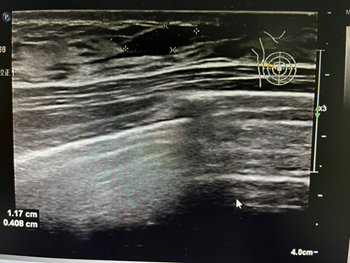

单纯性单发囊肿,BI-RADS  2类

假体植入后腺体层单发性囊肿,BI-RADS  2类